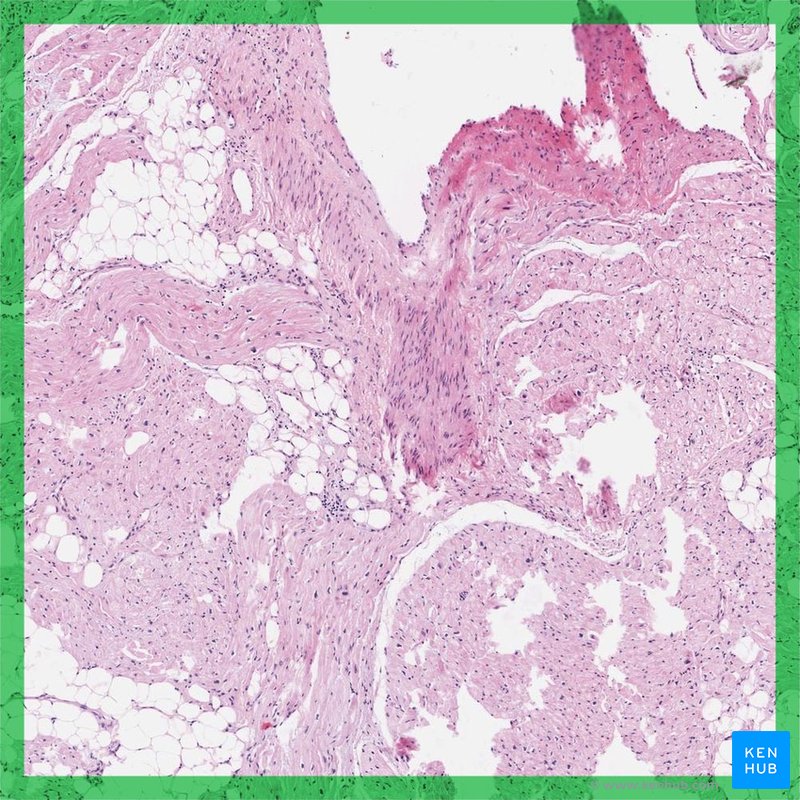

Heart layers

As the heart tubes fuse, the primordial myocardium begins to form from the splanchnic mesoderm around the pericardial cavity. This primordial myocardium becomes the middle, muscular layer of the heart. Separated from the primordial myocardium by gelatinous tissue called cardiac jelly, the heart begins to develop as a thin tube. This endothelial tube becomes the endocardium, the innermost layer of the heart. Epicardium, the outermost layer, originates from mesothelial cells from the outer surface of the sinus venosus.